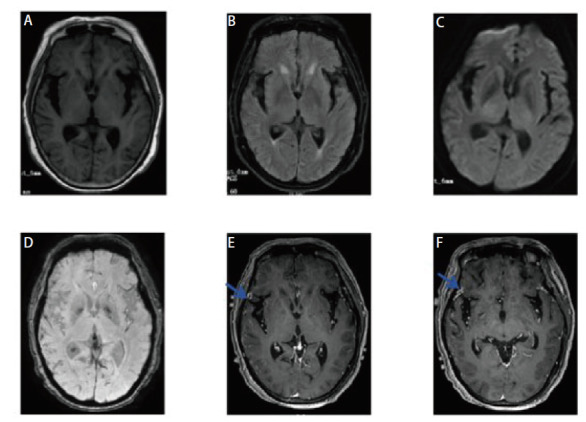

肺癌仍然是世界上最常见的恶性肿瘤之一。随着发病率的增加和医疗技术的发展,肺癌患者的总体生存期较以往有了明显延长。肺癌脑、脑膜转移的发病率也逐年上升,但肺癌脑、脑膜转移患者预后差,死亡率非常高,诊断主要依靠计算机断层扫描(CT)、磁共振成像(MRI)等影像学检查。但其影像学特征多样,特异性低,易误诊漏诊。因此,准确识别脑及脑膜转移灶并及时进行靶向治疗对改善患者预后至关重要。本文分析1例肺癌根治性手术后近7年长期随访无明显复发转移,但近5个月患者行为异常、意识受损、癫痫,头部CT及MRI发现脑内多发点状钙化的诊断与治疗。本文认为患者的精神和行为症状是在排除感染性疾病和自身免疫性脑炎治疗无效后,由肺癌脑、脑膜转移引起的,进一步病理活检和基因检测证实为表皮生长因子受体(EGFR) L858R基因突变的转移性肺腺癌,经奥西替尼靶向治疗后,患者症状得到明显改善。本文还在中国知网、万方、UpToDate、PubMed等数据库中检索了脑钙化的相关文献,发现脑钙化存在于多种疾病中,包括感染性疾病、遗传性和神经退行性疾病、血管疾病、代谢疾病和肿瘤。然而,脑钙化和脑膜转移往往被低估,随之而来的风险是误诊和延误治疗。因此,在既往有肿瘤病史的患者中,表现为脑钙化的脑和脑膜转移不应被忽视。

Lung cancer is still one of the most common malignant tumors in the world. With the increase of its incidence and the development of medical technology, the overall survival of lung cancer patients has significantly extended compared to before. The incidence of brain and meningeal metastases from lung cancer has also been rising year by year, but patients with brain and meningeal metastases from lung cancer have a poor prognosis and a very high mortality rate, and the diagnosis is mainly based on computed tomography (CT), magnetic resonance imaging (MRI) and other imaging examinations. However, the imaging features are diverse and the specificity is low, which makes it easy to be misdiagnosed and missed. Therefore, accurately identifying brain and meningeal metastases and timely targeted treatment is crucial for improving patient prognosis. This paper analyzed the diagnosis and treatment of a case of lung cancer with no obvious recurrence and metastasis in nearly 7-year long-term follow-up after radical lung cancer surgery, but the patient with abnormal behavior, impaired consciousness and epilepsy in the past 5 months, and multiple punctate calcifications in the brain found by head CT and MRI. This paper consider that the patient's mental and behavioral symptoms were caused by brain and meningeal metastasis of lung cancer after excluding infectious disease and ineffective treatment of autoimmune encephalitis, and further pathological biopsy and genetic detection confirmed the diagnosis of metastatic lung adenocarcinoma with epidermal growth factor receptor (EGFR) L858R gene mutation, and the patient's symptoms were significantly improved after targeted therapy by Osimertinib. This paper also searched the relevant literatures of brain calcifications in databases such as China National Knowledge Infrastructure (CNKI), Wanfang, UpToDate, PubMed, etc., and found that intracerebral calcifications exist in a variety of diseases, including infectious, genetic and neurodegenerative diseases, vascular diseases, metabolic diseases and tumors. However, brain calcification in brain and meningeal metastases are often underestimated, and the consequent risk is misdiagnosis and delayed treatment. Therefore, brain and meningeal metastases manifested as brain calcification should not be ignored in patients with a history of previous tumors.